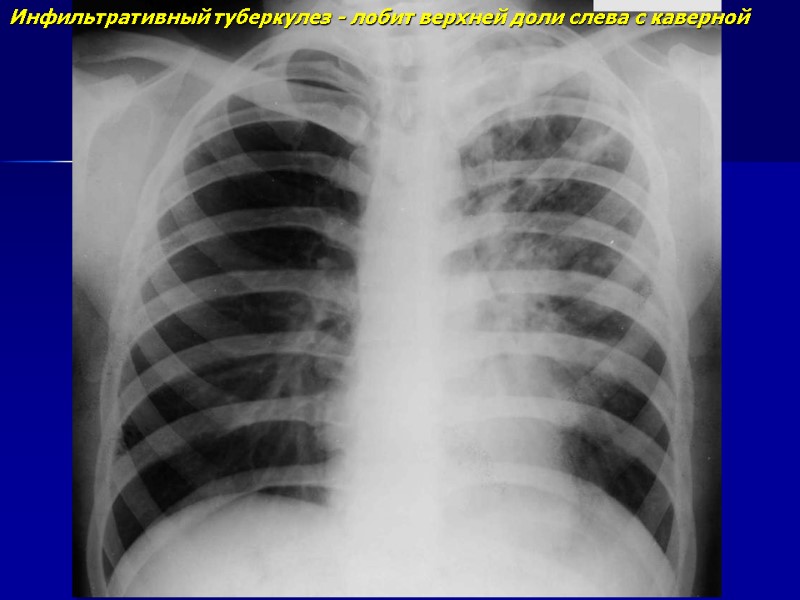

Инфильтративный туберкулез - лобит верхней доли слева с каверной